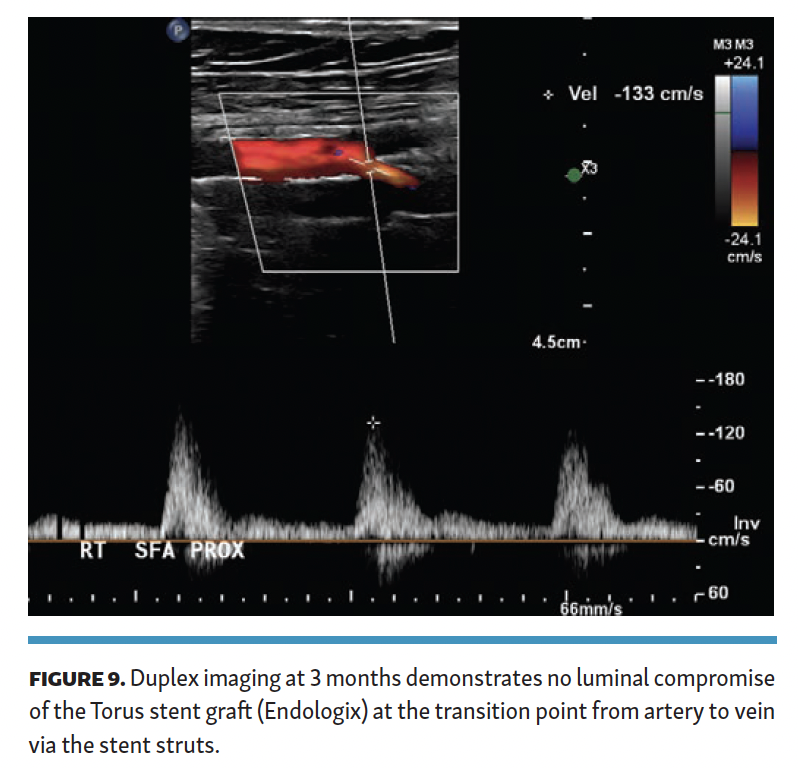

The patient was maintained on oral anticoagulation and aspirin. ABI at 6-month follow-up was 1.09, and she had no claudication symptoms. Duplex imaging of the Torus stent graft exiting the SFA across the stent into the femoral vein demonstrated no stenosis (Figure 9), with no velocity elevation at the proximal or distal end of the Torus stent. Duplex imaging did not demonstrate DVT in any of the veins in the target limb.